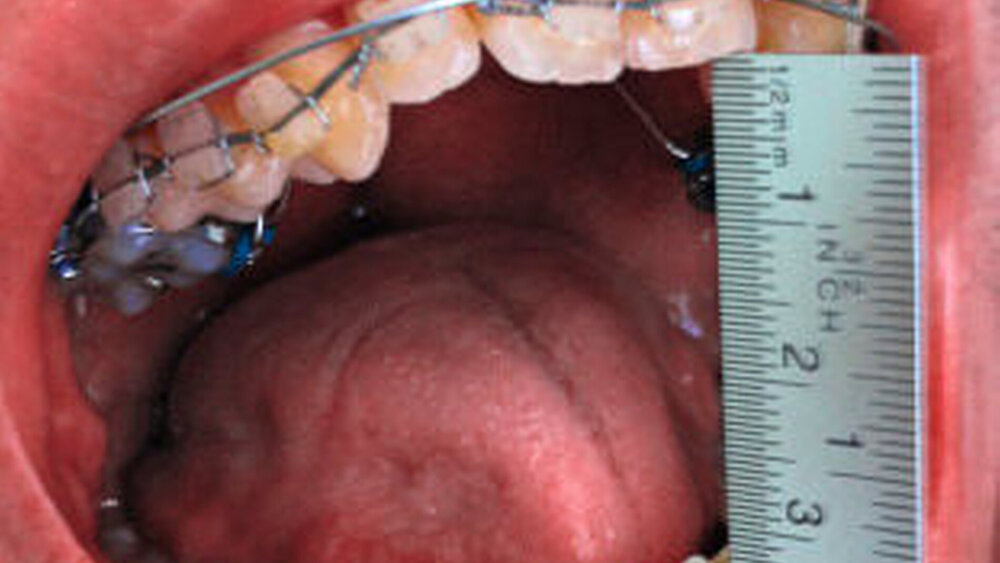

Im Rahmen des Gesprächs berichtete der Patient über eine schmerzfreie, jedoch eingeschränkte Mundöffnung, die er bisher aber nicht hatte untersuchen lassen. Die spezielle Anamnese lieferte keine Hinweise für eine mögliche Ursache der eingeschränkten Mundöffnung. Während der klinischen Untersuchung konnte eine Mundöffnung von 20 mm (SKD) gemessen werden (Abbildung 1).